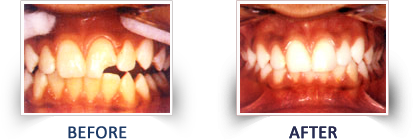

These materials represent the latest range of cosmetic filling materials, which have a property of bonding to the tooth structure. These materials find their application in many cases like filling of the front and the back teeth, which are decayed, broken, chipped, discolored as well as in cases where there are gaps between the teeth.

The life like appearance of composite filling materials makes it difficult to distinguish between the filling and the sound tooth structure. This property in particular, makes it the most popular filling material. Composite resin dental fillings or white fillings are tooth fillings colored to look like a natural tooth.

1) Aesthetics – shade/color can be matched to existing teeth well suited for front teeth use

2) Versatility in uses – in addition to use as a filling material for decay, composite fillings can also be used to repair chipped, broken or worn teeth

Composite Filling (Tooth Colored Filling)